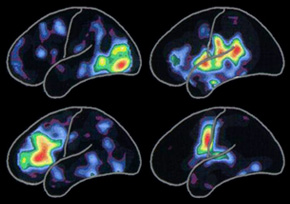

左圖所顯示的陽電子釋放 X 線斷層掃瞄(PET scan)顯示不同腦部活動的模式:

閱讀(左上)

聆聽詞語(右上)

思考詞語(左下)

說出詞語(右下)

紅色的部份表示該區活動是最活躍的,其次活躍的到黃色和紫藍色。